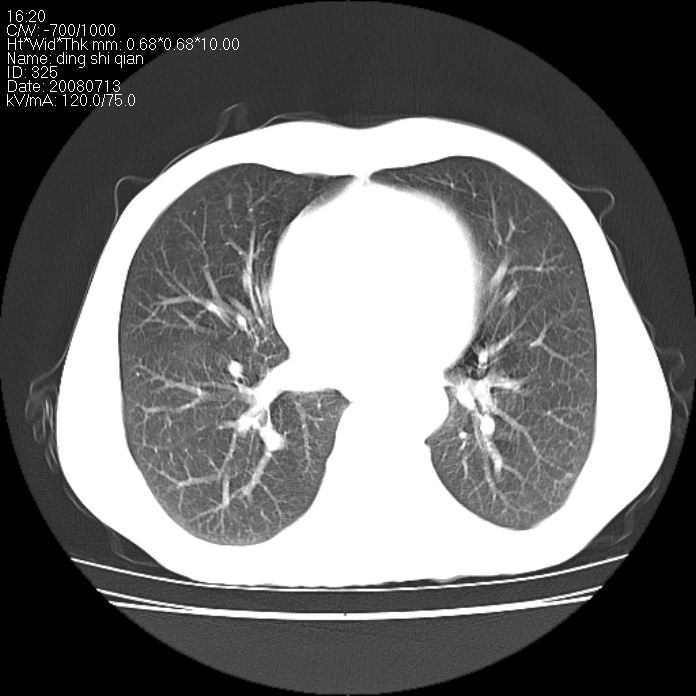

标题: CT14654:男 50岁 近来胸痛 [打印本页]

标题: CT14654:男 50岁 近来胸痛

右侧上肺块状软组织影,浅分叶,边缘毛刺证,与胸膜粘连,考虑:周围性肺癌

首先考虑周围性肺癌,建议强化或穿刺明确

考虑: 右肺上叶周围型肺癌可能性大.

右肺上叶周围型肺癌。

右肺上叶周围型肺癌可能性大。